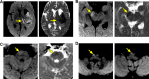

Methods and results: Consecutive ICH patients with supratentorial ICH prospectively underwent serial MRIs at 2, 7, 14, and 21 days. MRIs were analyzed by independent raters for the presence and topographical distribution of CST-WD on diffusion-weighted imaging (DWI). Baseline demographics, hematoma characteristics, ICH score, and admission National Institute of Health Stroke Score (NIHSS) were systematically recorded. Functional outcome at 3 months was assessed by the modified Rankin Scale (mRS) and the motor-NIHSS. Twenty-seven patients underwent 93 MRIs; 88 of these were serially obtained in the first month. In 13 patients (48%), all with deep ICH, CST-WD changes were observed after a median of 7 days (interquartile range, 7 to 8) as reduced diffusion on DWI and progressed rostrocaudally along the CST. CST-WD changes evolved into T2-hyperintense areas after a median of 11 days (interquartile range, 6 to 14) and became atrophic on MRIs obtained after 3 months. In univariate analyses, the presence of CST-WD was associated with poor functional outcome (ie, mRS 4 to 6; P=0.046) and worse motor-NIHSS (5 versus 1, P=0.001) at 3 months.

Conclusions: Wallerian degeneration along the CST is common in spontaneous supratentorial ICH, particularly in deep ICH. It can be detected 1 week after ICH on DWI and progresses rostrocaudally along the CST over time. The presence of CST-WD is associated with poor motor and functional recovery after ICH.